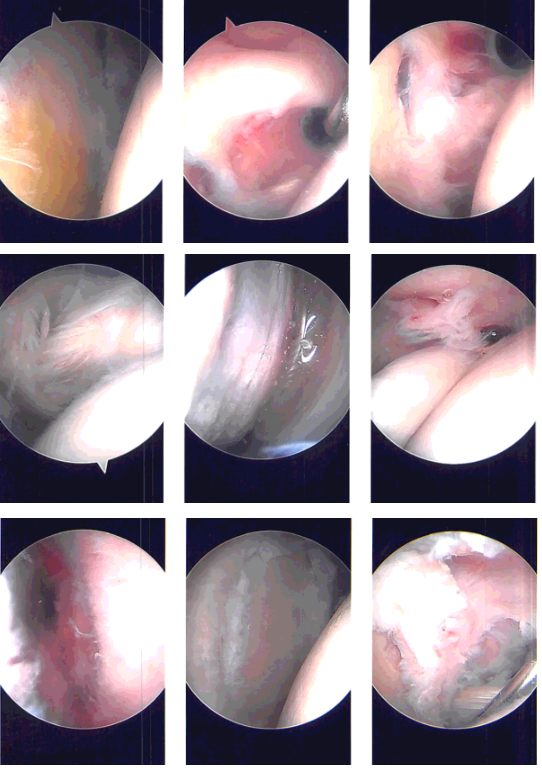

Arthroscope was entered and examination of the glenohumeral joint showed degeneration of the glenoid labrum with tear of the superior labrum and biceps anchor. There was tearing of the subscapularis muscle as well as supraspinatus on the articular side.

Shaver was used for debridement of the rotator cuff. Straight biter was used to cut the biceps and glenoid labrum was debrided using a shaver. Rest of the examination of the shoulder joint was normal. All the pictures were saved.

The arthroscope was entered into the subacromial space, where subacromial bursitis was present. The subacromial bursitis was debrided using a shaver through an anteromedial portal. A lateral portal was made. The scope was entered through the lateral portal and further debridement was done.

Acromioplasty was performed using a thermal wand followed by a shaver. AC arthritis was seen. Distal clavicular excision was performed using the thermal wand and burr. Rotator cuff was examined and found to be intact on the bursal side. Pictures were taken and saved.

Intraoperative Arthroscopy Images